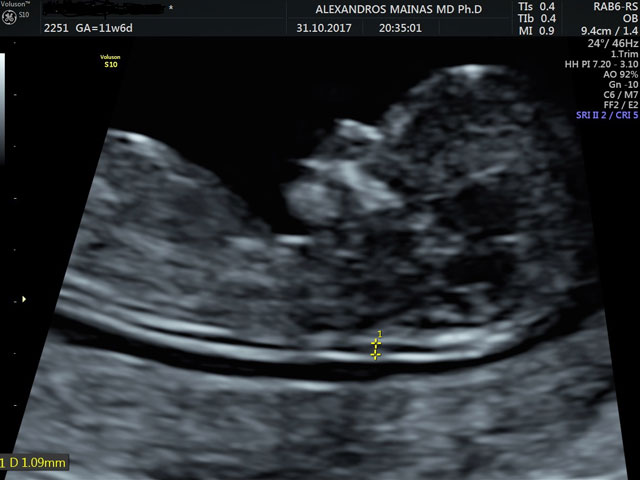

Έλεγχος της αυχενικής διαφάνειας

Το 1866 ο Langdon Down παρατήρησε ότι το δέρμα των ατόμων με τρισωμία 21 ήταν παχύτερο από τα φυσιολογικά άτομα. Το 1992 ο καθηγητής κ. Κ. Νικολαΐδης ανακάλυψε ότι αυτή η πάχυνση μπορεί να παρατηρηθεί υπερηχογραφικά στον 3ο μήνα της κύησης, ως συσσώρευση υγρού στον αυχένα του εμβρύου και ονομάστηκε αυχενική διαφάνεια. Τα τελευταία 20 χρόνια ακολούθησαν εκτεταμένες μελέτες όπου αποδείχθηκε ότι η αυξημένη αυχενική διαφάνεια σχετίζεται άμεσα με χρωμοσωμικές ανωμαλίες, καρδιακές βλάβες και μερικά γενετικά σύνδρομα του εμβρύου. Έτσι πλέον η μέτρηση της εφαρμόζεται σε όλες τις κυήσεις μεταξύ της 11ης και 14ης εβδομάδας σύμφωνα με  ορισμένα στάνταρ, τα οποία διέπουν τη μέτρησή της ώστε το αποτέλεσμα να είναι αξιόπιστο.

Την τελευταία διετία στον παραπάνω συνδυασμό προστέθηκαν και νέοι υπερηχογραφικοί δείκτες πέρα από το γνωστό ρινικό οστό όπως η αυξημένη αντίσταση στη ροή του φλεβώδους πόρου και η ανεπάρκεια της τριγλώχινας βαλβίδας της καρδιάς του εμβρύου. Είναι γνωστό ότι η απουσία του ρινικού οστού ή παθολογική ροή στο φλεβώδη πόρο (αντιστροφή κύματος α) και η ανεπάρκεια στην τριγλώχινα βαλβίδα της καρδιάς παρατηρούνται σε έμβρυα με τρισωμία 21 σε ποσοστά  60, 65, 55% αντίστοιχα, ενώ σε φυσιολογικά έμβρυα σε ποσοστά 2,5, 3 και 1%.

• Μετρηθεί η αυχενική διαφάνεια του εμβρύου